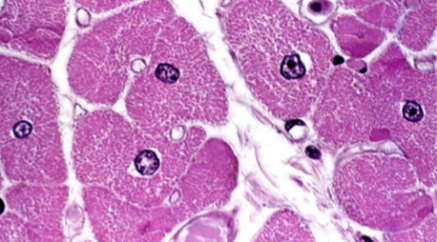

term image

Skeletal muscle

Location: Attached to bones

Function: Movement, posture, heat

Key features of ID: Striations or dots, nuclei on the periphery, multinucleated.